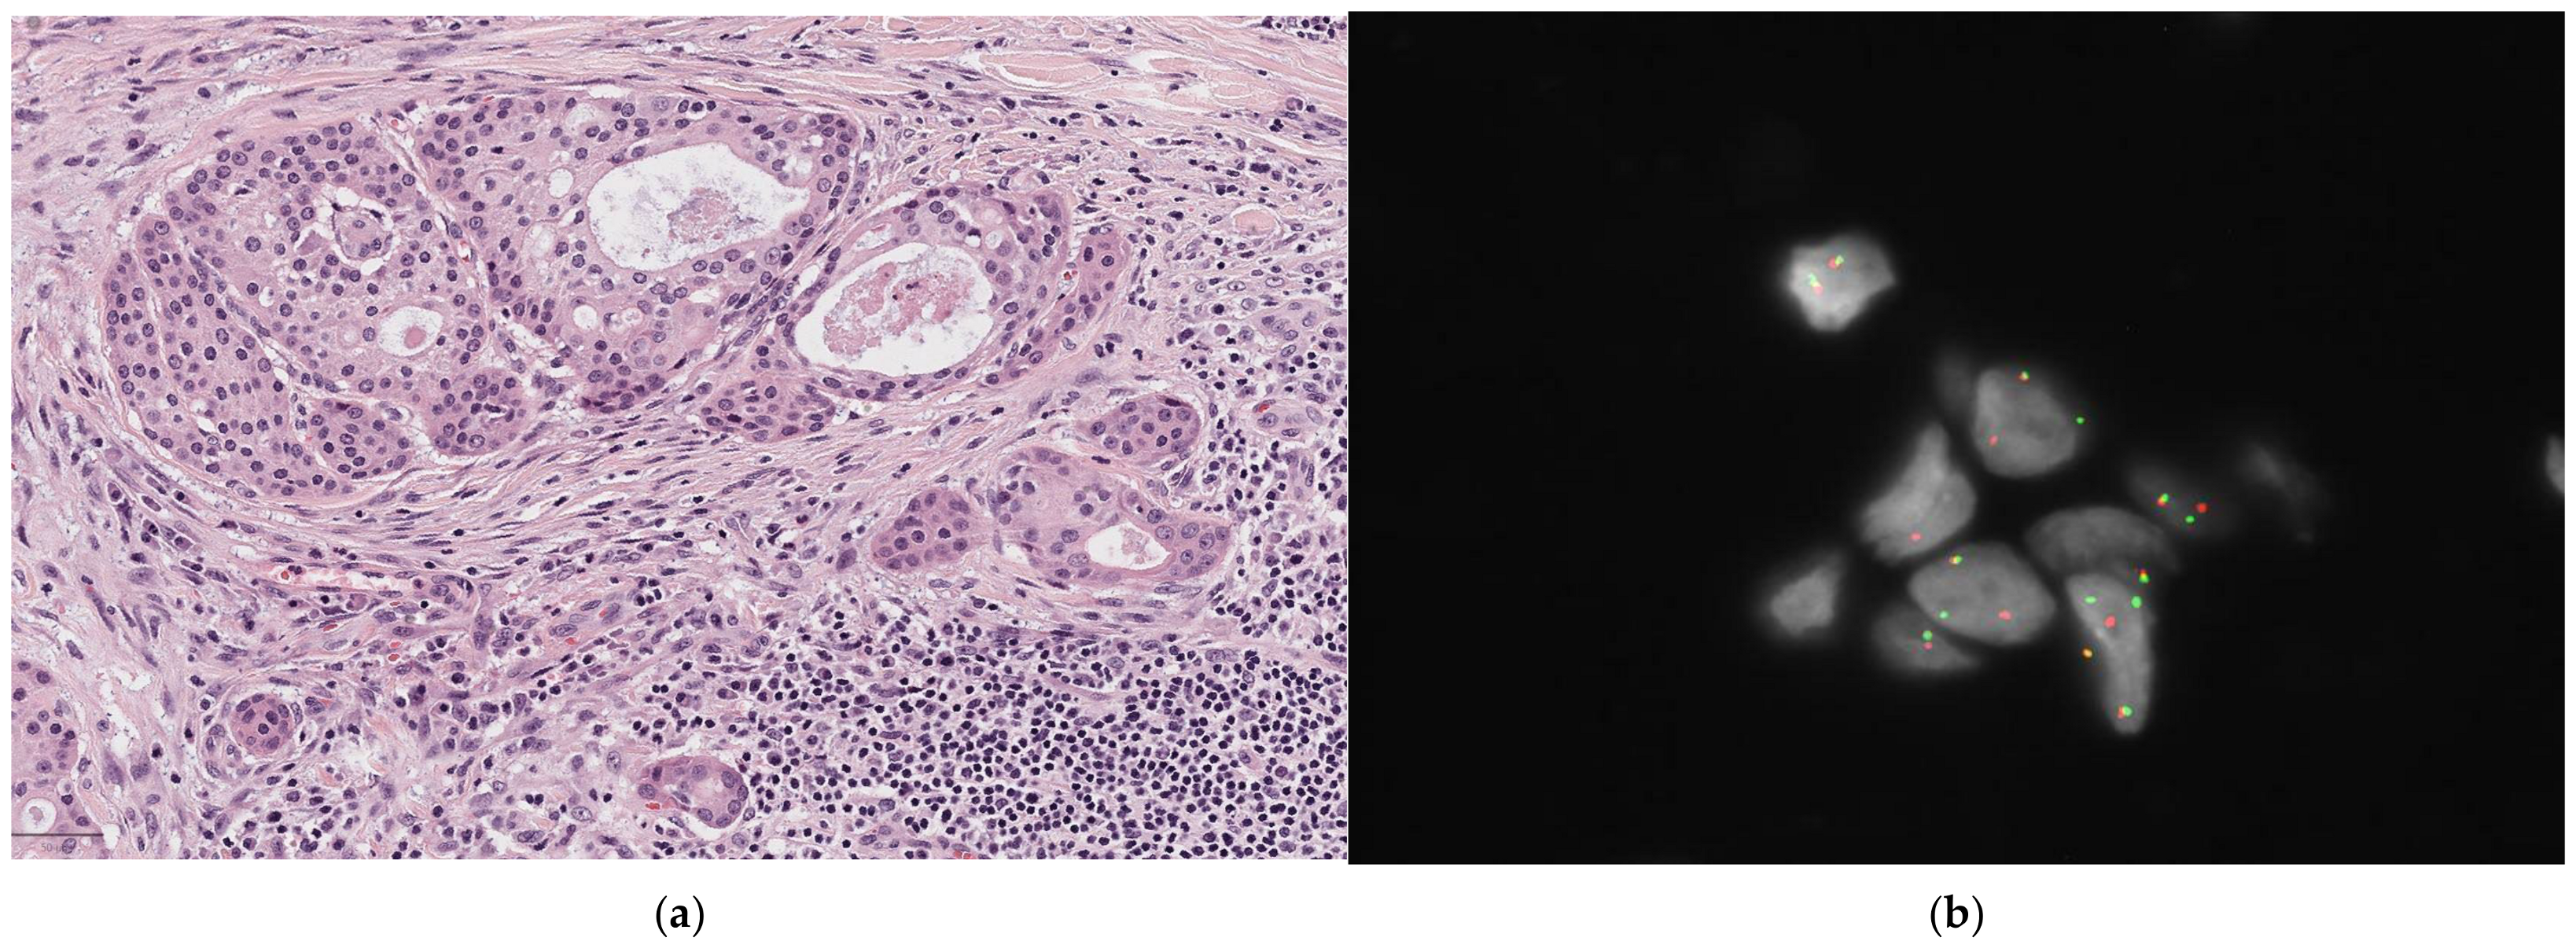

Pathologically, these lymphoma cells often show angiocentricity and angiodestruction, resulting in zonal necrosis. Extensive inflammation associated with a tumor makes diagnosis difficult because of the high risk of false negatives. ENKTL exhibits a polymorphous infiltration of neoplastic cells mixed with inflammatory cells; a florid pseudoepitheliomatous hyperplasia of the overlying squamous epithelium could be present [Figure 6a]. The cytomorphology of the tumor cells varies and is most often composed of medium-sized cells or a mixture of small and large lymphocytes with hyperchromatic and irregular nuclei. The typical immunophenotype of ENKTL is CD20−, sCD3−, cCD3+, CD4−, CD5−, CD8−, and CD56+, with the expression of cytotoxic molecules such as TIA1, granzyme B, and perforin [106]. Lymphoma cells are almost invariably infected by EBV, which exists in a clonal episomal form that is not integrated into the host genome [107]. EBV infection is typically identified through EBER, which is a prerequisite for diagnosing NK/T-cell lymphoma, but this alone is insufficient [Figure 6b]. Either CD56 or cytotoxic molecules must also be present for a definitive diagnosis [Figure 6c] [108].

Figure 6.

Extranodal NK/T-cell lymphoma (ENKTL). (a) (10×) The lymphoma shows medium to large tumor cells with irregular and often hyperchromatic nuclei associated with nested hyperplastic squamous epithelium; (b) positive labelling of the tumor cell nuclei for EBV-encoded small RNAs (EBERs) on in situ hybridization; (c) positive CD56 in neoplastic cells.

Regarding molecular pathology, conventional karyotyping has identified the deletion of chromosome 6q (6q–) as a recurrent cytogenetic aberration in NK/T-cell lymphoma; gene expression profiling (GEP) has shown similarities between NK/T-cell lymphoma and peripheral T-cell lymphoma (PTCL) of the gamma/delta subtype. Additionally, exome sequencing has revealed activating mutations in STAT3 and STAT5B in a significant number of cases. Next-generation sequencing has identified mutations in the RNA helicase gene DDX3X in approximately 20% of cases, TP53 mutations in about 13%, and, more rarely, alterations in genes involved in epigenetic pathways—such as MLL, ASXL1, ARID1A, and EP300 [106].